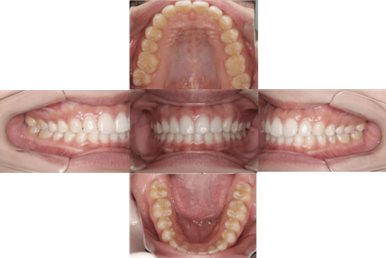

症例 ①

●マウスピース 部分矯正 ●23歳 ●治療期間:6ヶ月 ●費用:40万円

- 治療前 -

- 治療後 -

▶︎マウスピースを用いて、前歯の隙間・捻れの治療を行いました。